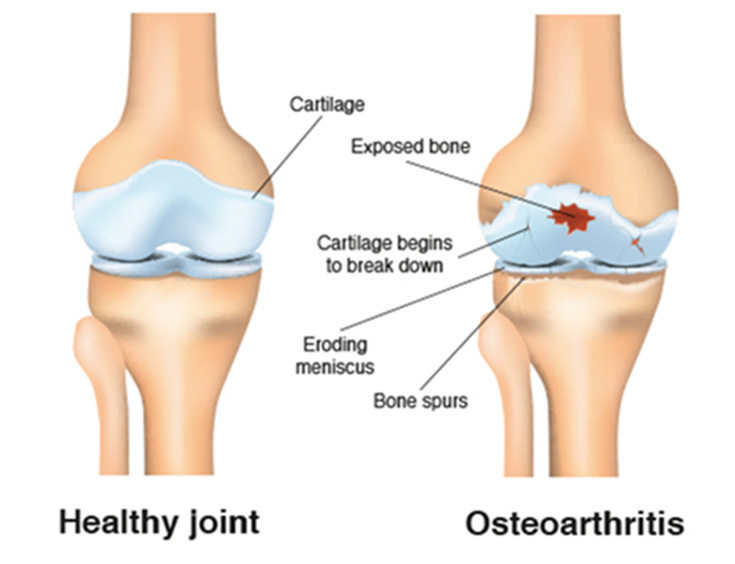

As with other types of arthritis, women are at higher risk than men for the condition. Osteoarthritis affects structures throughout the joint. Among them the cartilage, the slippery tissue that covers the ends of bones in a joint, is usually affected. Healthy cartilage allows bones to glide over one another and absorbs energy from the shock of physical movement.

In osteoarthritis, the surface layer of cartilage breaks down and wears away, which allows bones under the cartilage to rub together. This causes bone remodeling and change in boney shape and loss of motion of the joint. Over time, the joint loses its normal shape. Also, bone spurs—small growths called osteophytes—may grow on the edges of the joint. By the time a person has symptoms from osteoarthritis, it is no longer just a disease of cartilage. Bone has changed, muscles across the joint have often weakened and there is occasionally inflammation in the lining of the joint.

Osteoarthritis can occur in any joint but most often occurs at the joints in the hands, hips and knees.

- Knees: The knees are among the body’s main weight-bearing joints. They are also among the joints most commonly affected by osteoarthritis. An afflicted knee may be stiff, swollen and painful, making it hard to walk, climb or get in and out of chairs and bathtubs. If not treated, osteoarthritis in the knee can lead to disability. However, even with treatment, osteoarthritis may progress. Medications, losing weight, exercise and walking aids can reduce pain and disability. In severe cases, knee replacement surgery may be required. Research studies show that being overweight increases the risk of developing osteoarthritis of the knees and show that injuries to the knee are a major cause of disease.

- Osteoarthritis occurs when the surface layer of cartilage—the protective tissue between bones at joints—breaks down and wears away. This allows bones under the cartilage to rub together, causing pain, swelling and loss of motion of the joint.

- What causes osteoarthritis?In osteoarthritis, the surface layer of cartilage breaks down and wears away. This allows bones under the cartilage to rub together, causing pain, swelling and loss of motion of the joint. Major injuries to the joint, like tears of ligaments or of the meniscus in the knee, can also lead to osteoarthritis.